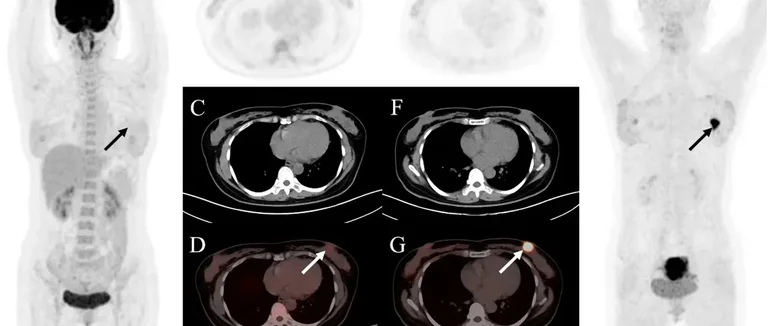

TEP-Scan

Le TEP-Scan utilise des traceurs radioactifs pour voir l'activité métabolique. Il est bon pour détecter les cancers et voir leur propagation. Il peut être combiné avec la TDM pour plus d'informations.

Techniques Hybrides (SPECT/CT)

Les techniques hybrides, comme la SPECT/CT, ont changé la scintigraphie osseuse. Elles combinent l'imagerie fonctionnelle et anatomique pour mieux localiser les problèmes.